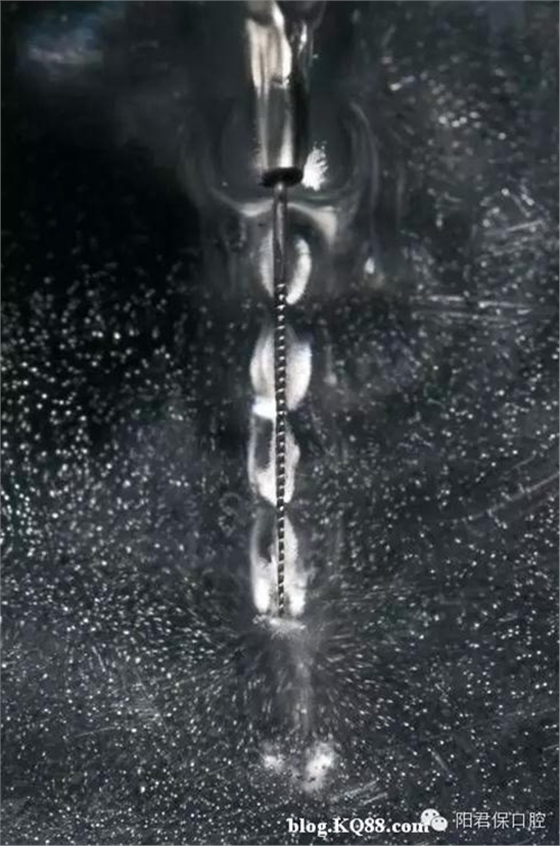

超聲蕩洗能增強清洗效果,超聲銼的持續(xù)震動可以將次氯酸鈉傳送到根尖部,也可以加熱根管內(nèi)的次氯酸鈉,超聲震動的頻率是25-40kHz,超聲在根管內(nèi)形成超聲流,同時在銼尖端形成渦流。超聲流有殺滅細菌和破壞酶的作用,超聲不能用于根管成形,只能用于根管蕩洗,所以根管塑形完成后再用超聲,否則可能會形成臺階或穿孔。

11.1超聲蕩洗的優(yōu)點有:

11.1.1增強沖洗劑去除碎屑的能力。

11.1.2促進沖洗劑溶解有機物和滅菌的能力。

11.1.3提高清理效果。

11.1.4減少內(nèi)容物推出根尖孔。

十二,超聲蕩洗的藥物 建議用2.5%或5.25%的次氯酸鈉

十三,超聲蕩洗的方法 超聲銼非工作狀態(tài)提前插入根管試合適,量好長度,然后震動后再進入根管做上下1mm的運動,盡量深入根管距離狹窄部2-3mm,但超聲銼絕不能碰觸到根管的任何部位。